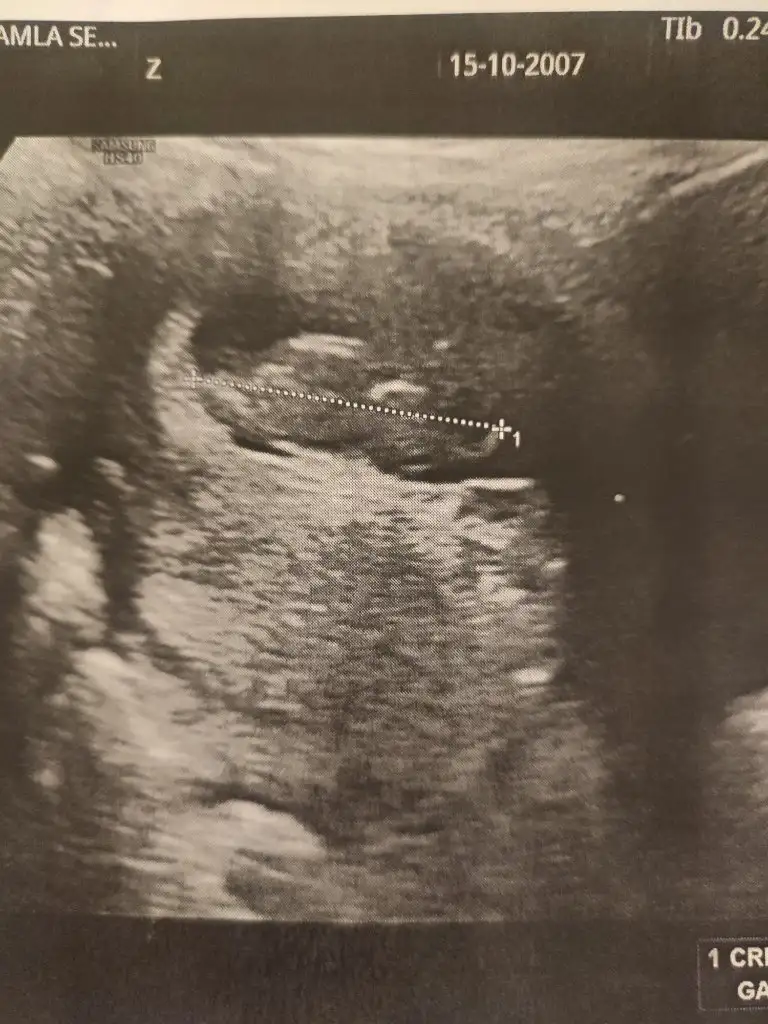

merhabalar benimkinde de tahminde bulunur musunuz 7 haftalık karından ultrason görüntüsü fotoğraftaki

Ramzi teorisi için daha küçük haftalardaki yani bebeğin kese içindeki yerleşimine göre bakıyorlar diye biliyorum. 7 ,8 haftalar gibi.

Burda ise eğer gördüğüm nub ise kız bebek tahminim. Gönlünüzce olur umarım 🙏